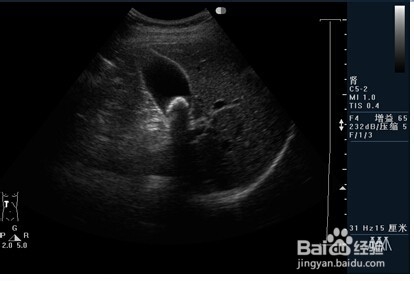

2、二:急性胆囊炎。